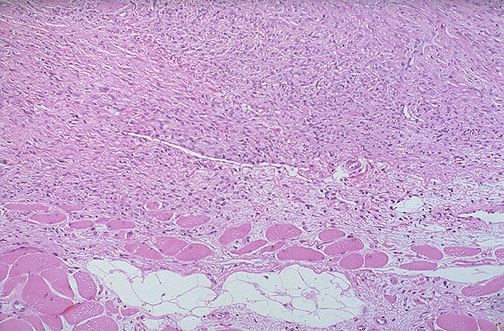

| This is another low grade lesion of soft tissue known as a desmoid tumor. These are aggressive fibroblastic proliferations that can occur in shoulder, chest wall, neck, and thigh in both men and women. In women during or just following pregancy, they may appear in abdominal wall. |